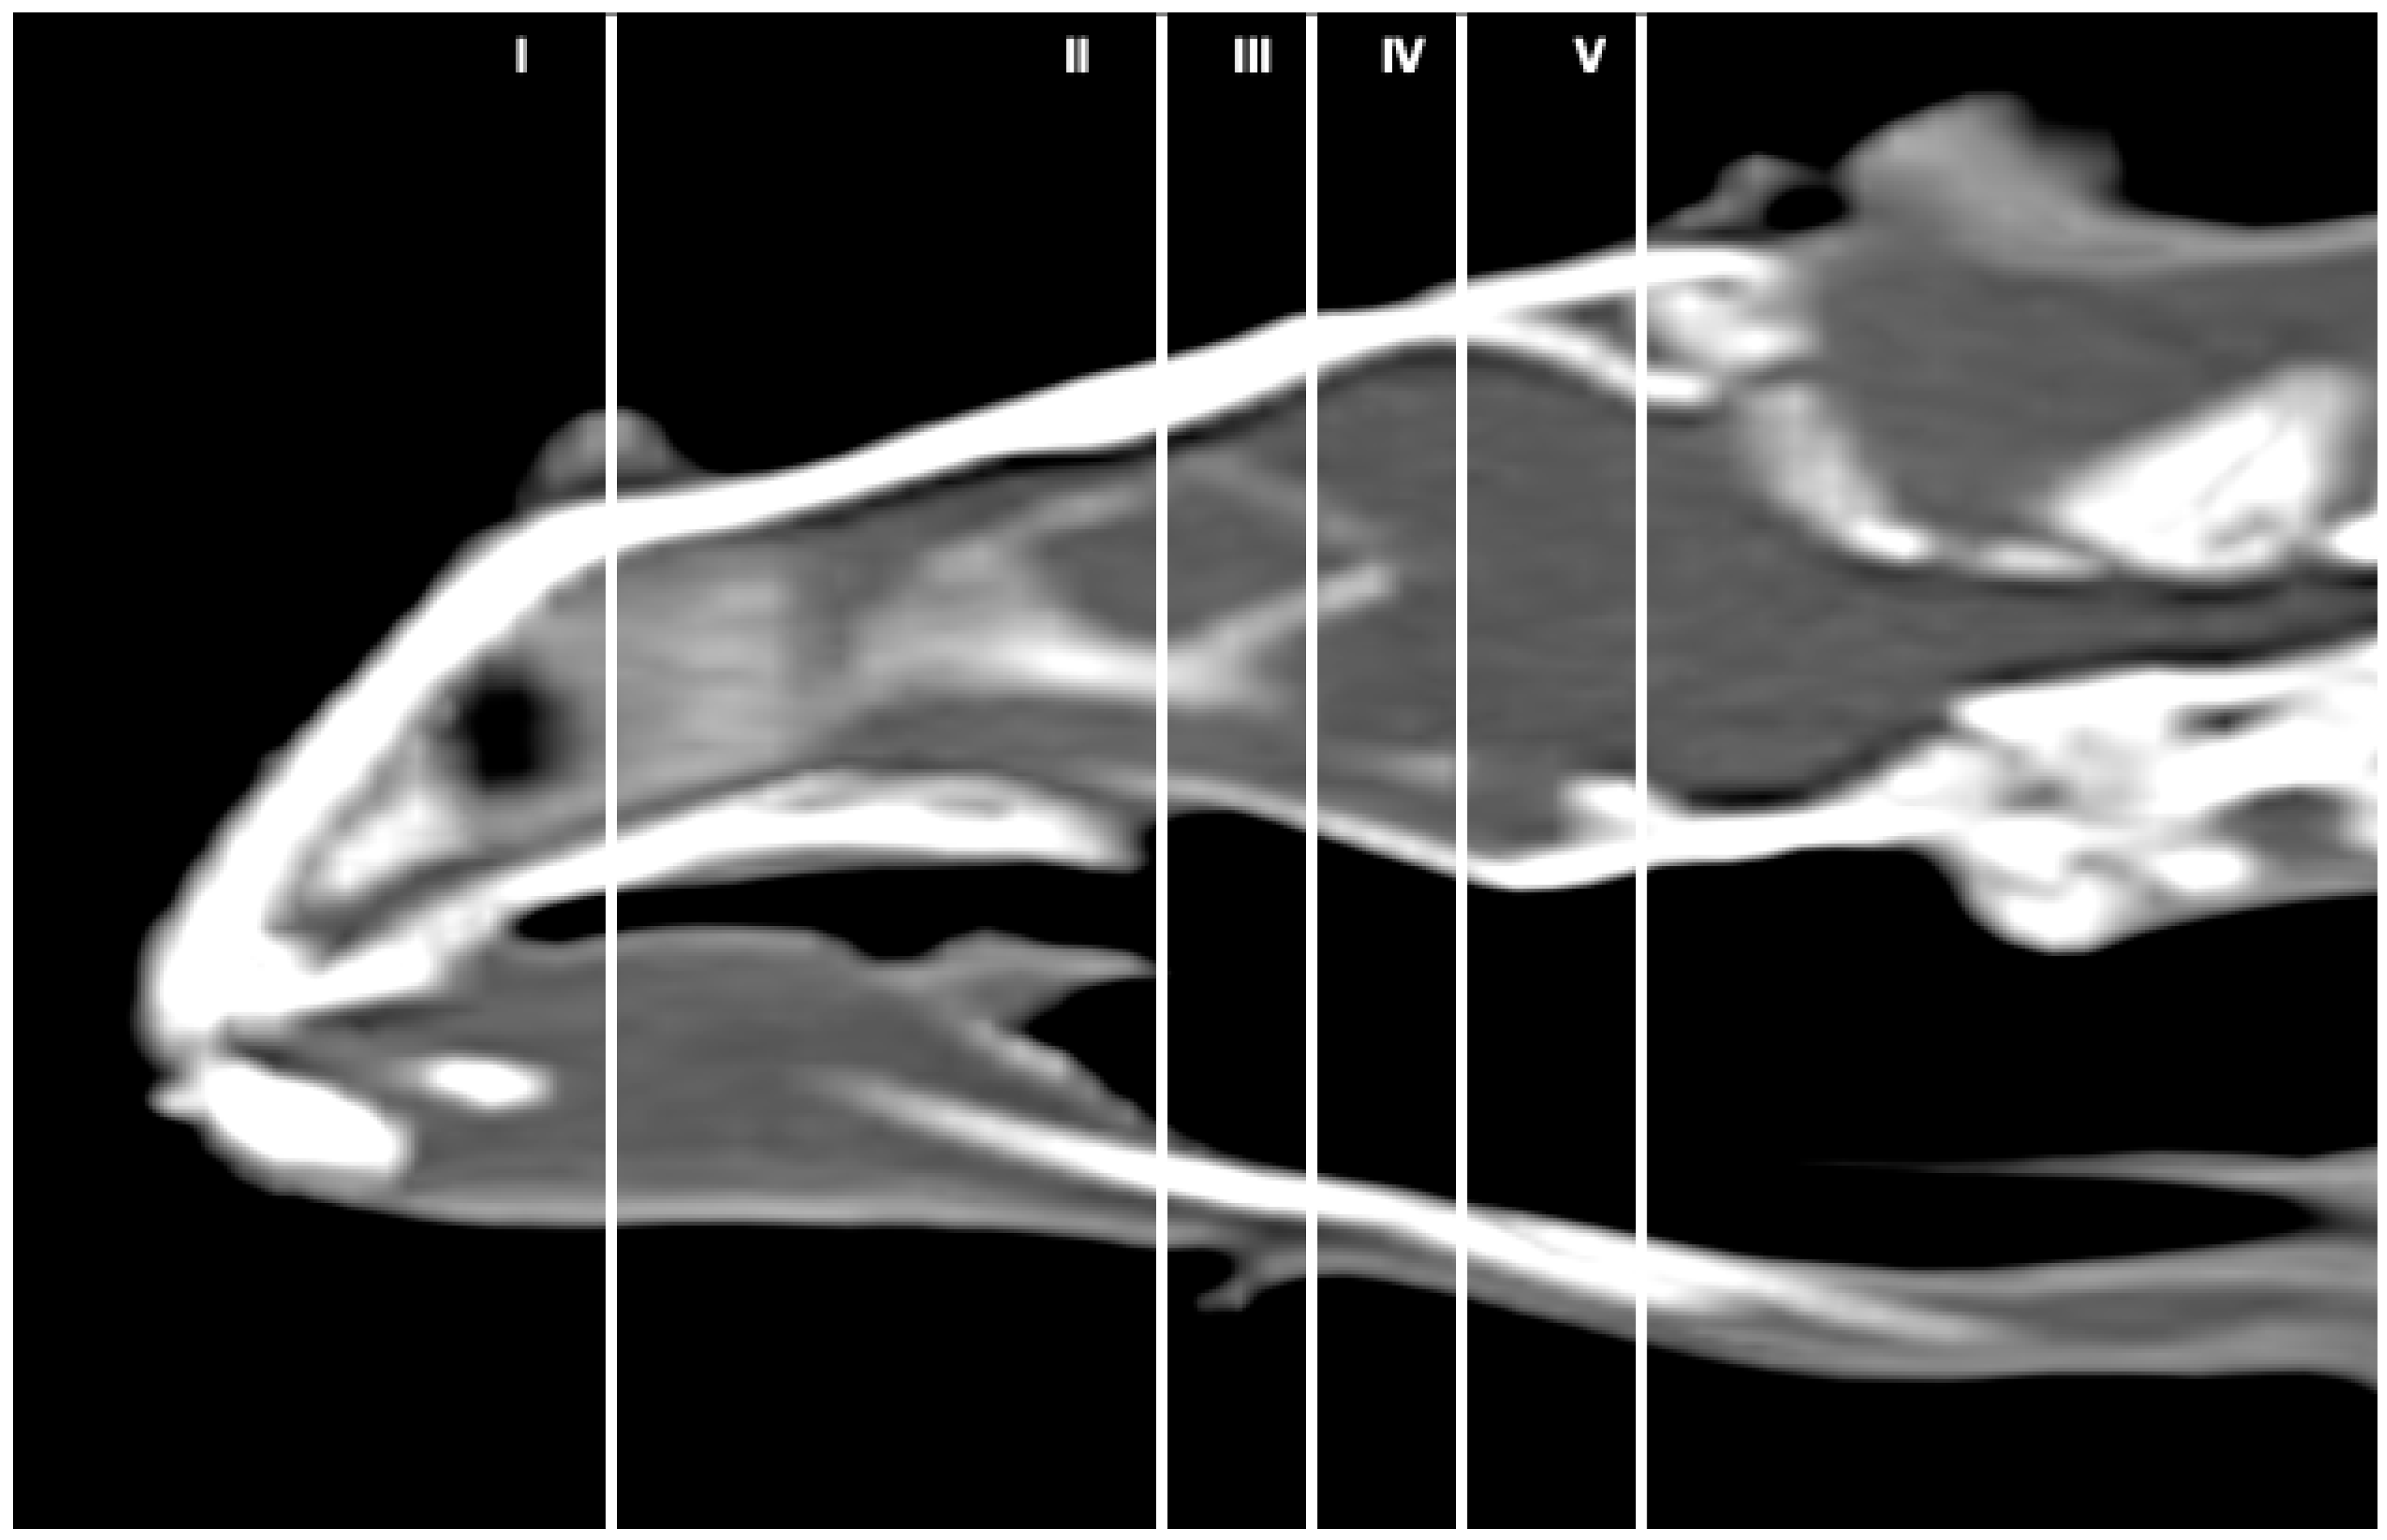

Figure 1 corresponds to a bone-window CT sagittal plane, in which each line and number (I–V) represents approximately the level of the following anatomical, CT and MRI transverse planes. Transversal sections revealing the relevant anatomical structures of the rhinoceros iguana head are presented (Figure 2, Figure 3, Figure 4, Figure 5 and Figure 6). Figure 2, Figure 3, Figure 4, Figure 5 and Figure 6 are composed of three images: (A) macroscopic, (B) bone window CT and (C) MRI. The images are presented in a rostrocaudal progression from the maxillary bone (Figure 2) to the brainstem levels (Figure 6). Figure 7 and Figure 8 are composed of two images: (A) bone-window CT and (B) MRI in T2W, in a dorsal and sagittal plane, respectively. Figure 9 is a T2W sequence sagittal image showing the angulation concerning the horizontal axis of the myelencephalon (40°).